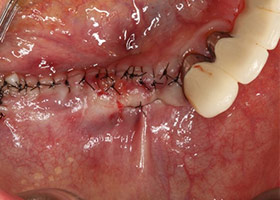

7.進行角質化牙齦移植手術。

8.牙齦手術完成。